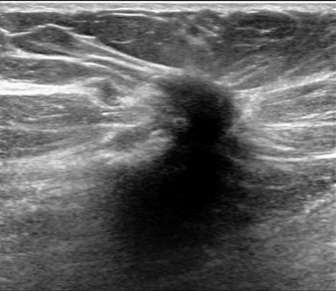

The above ultrasound demonstrates a hypoechoic (dark) mass with indistinct margins, posterior shadowing, and distortion of the normal breast tissue. This was biopsied, revealing invasive ductal carcinoma (IDC). Both ductal carcinoma in situ (DCIS) and IDC may result in distortion.